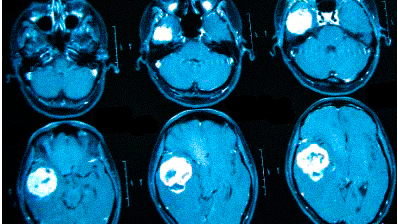

Онкологи считают, что при нарастающих головных болях с прочими необъяснимыми симптомами (обмороками, ухудшением памяти, выпадением полей зрения, давлением на глазные яблоки и др.) в первую очередь следует исключить опухолевую патологию

Частые головные боли вызывают разные причины. Иногда так проявляется серьезное заболевание. В 90% случаев после определения генеза возможно адекватное лечение, которое улучшит качество жизни. Состояния, для которых типична цефалгия::

Если причина не установлена, обосновано прохождение МРТ головы при головных болях. Не стоит подозревать у себя смертельную патологию. Например, если болит затылок, возможной причиной является переутомление, а нормализация режима труда и отдыха поможет справиться с проблемой. При повышенном давлении часто присутствует головокружение, покраснение кожных покровов, шум в ушах. Боль в лобной части головы вторична и проходит после приема гипотензивного лекарства. Но гипертония может быть связана с патологией сосудов или опухолевой компрессией, поэтому прохождение МРТ при сильных головных болях — важный аспект в дифференциальной диагностике.